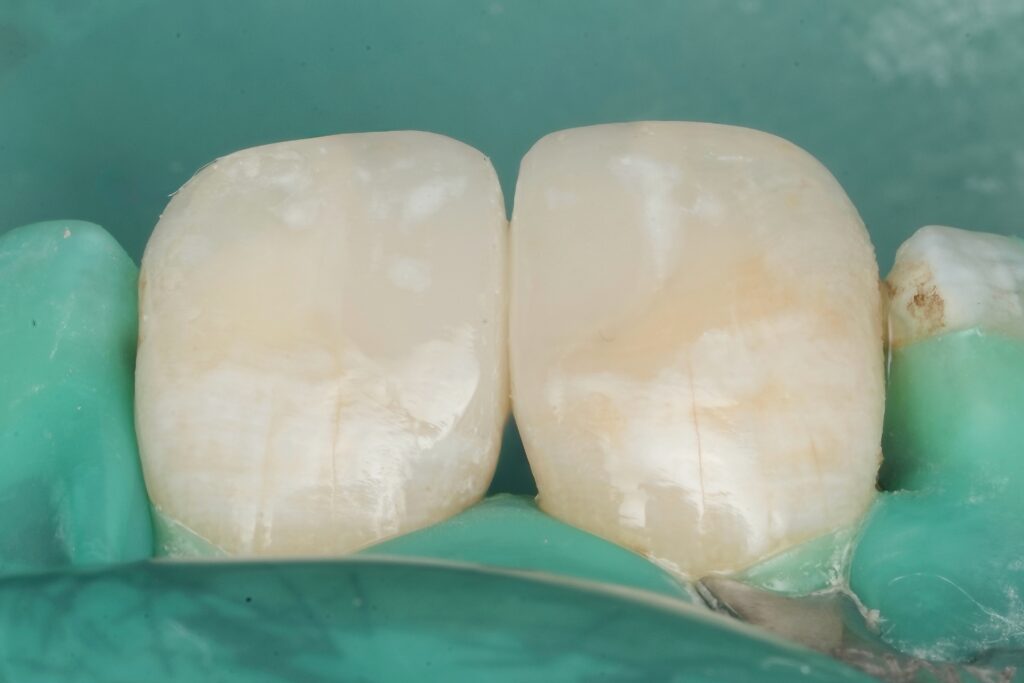

7) Build the proximal wall first (contact is created here)

This is the “restorography” mindset: rebuild anatomy in the correct order.

Step: Place a thin increment to create the proximal wall and cure thoroughly.

Once the wall is stable, you convert the case into a simple Class I, which dramatically improves control of anatomy and shrinkage vectors.